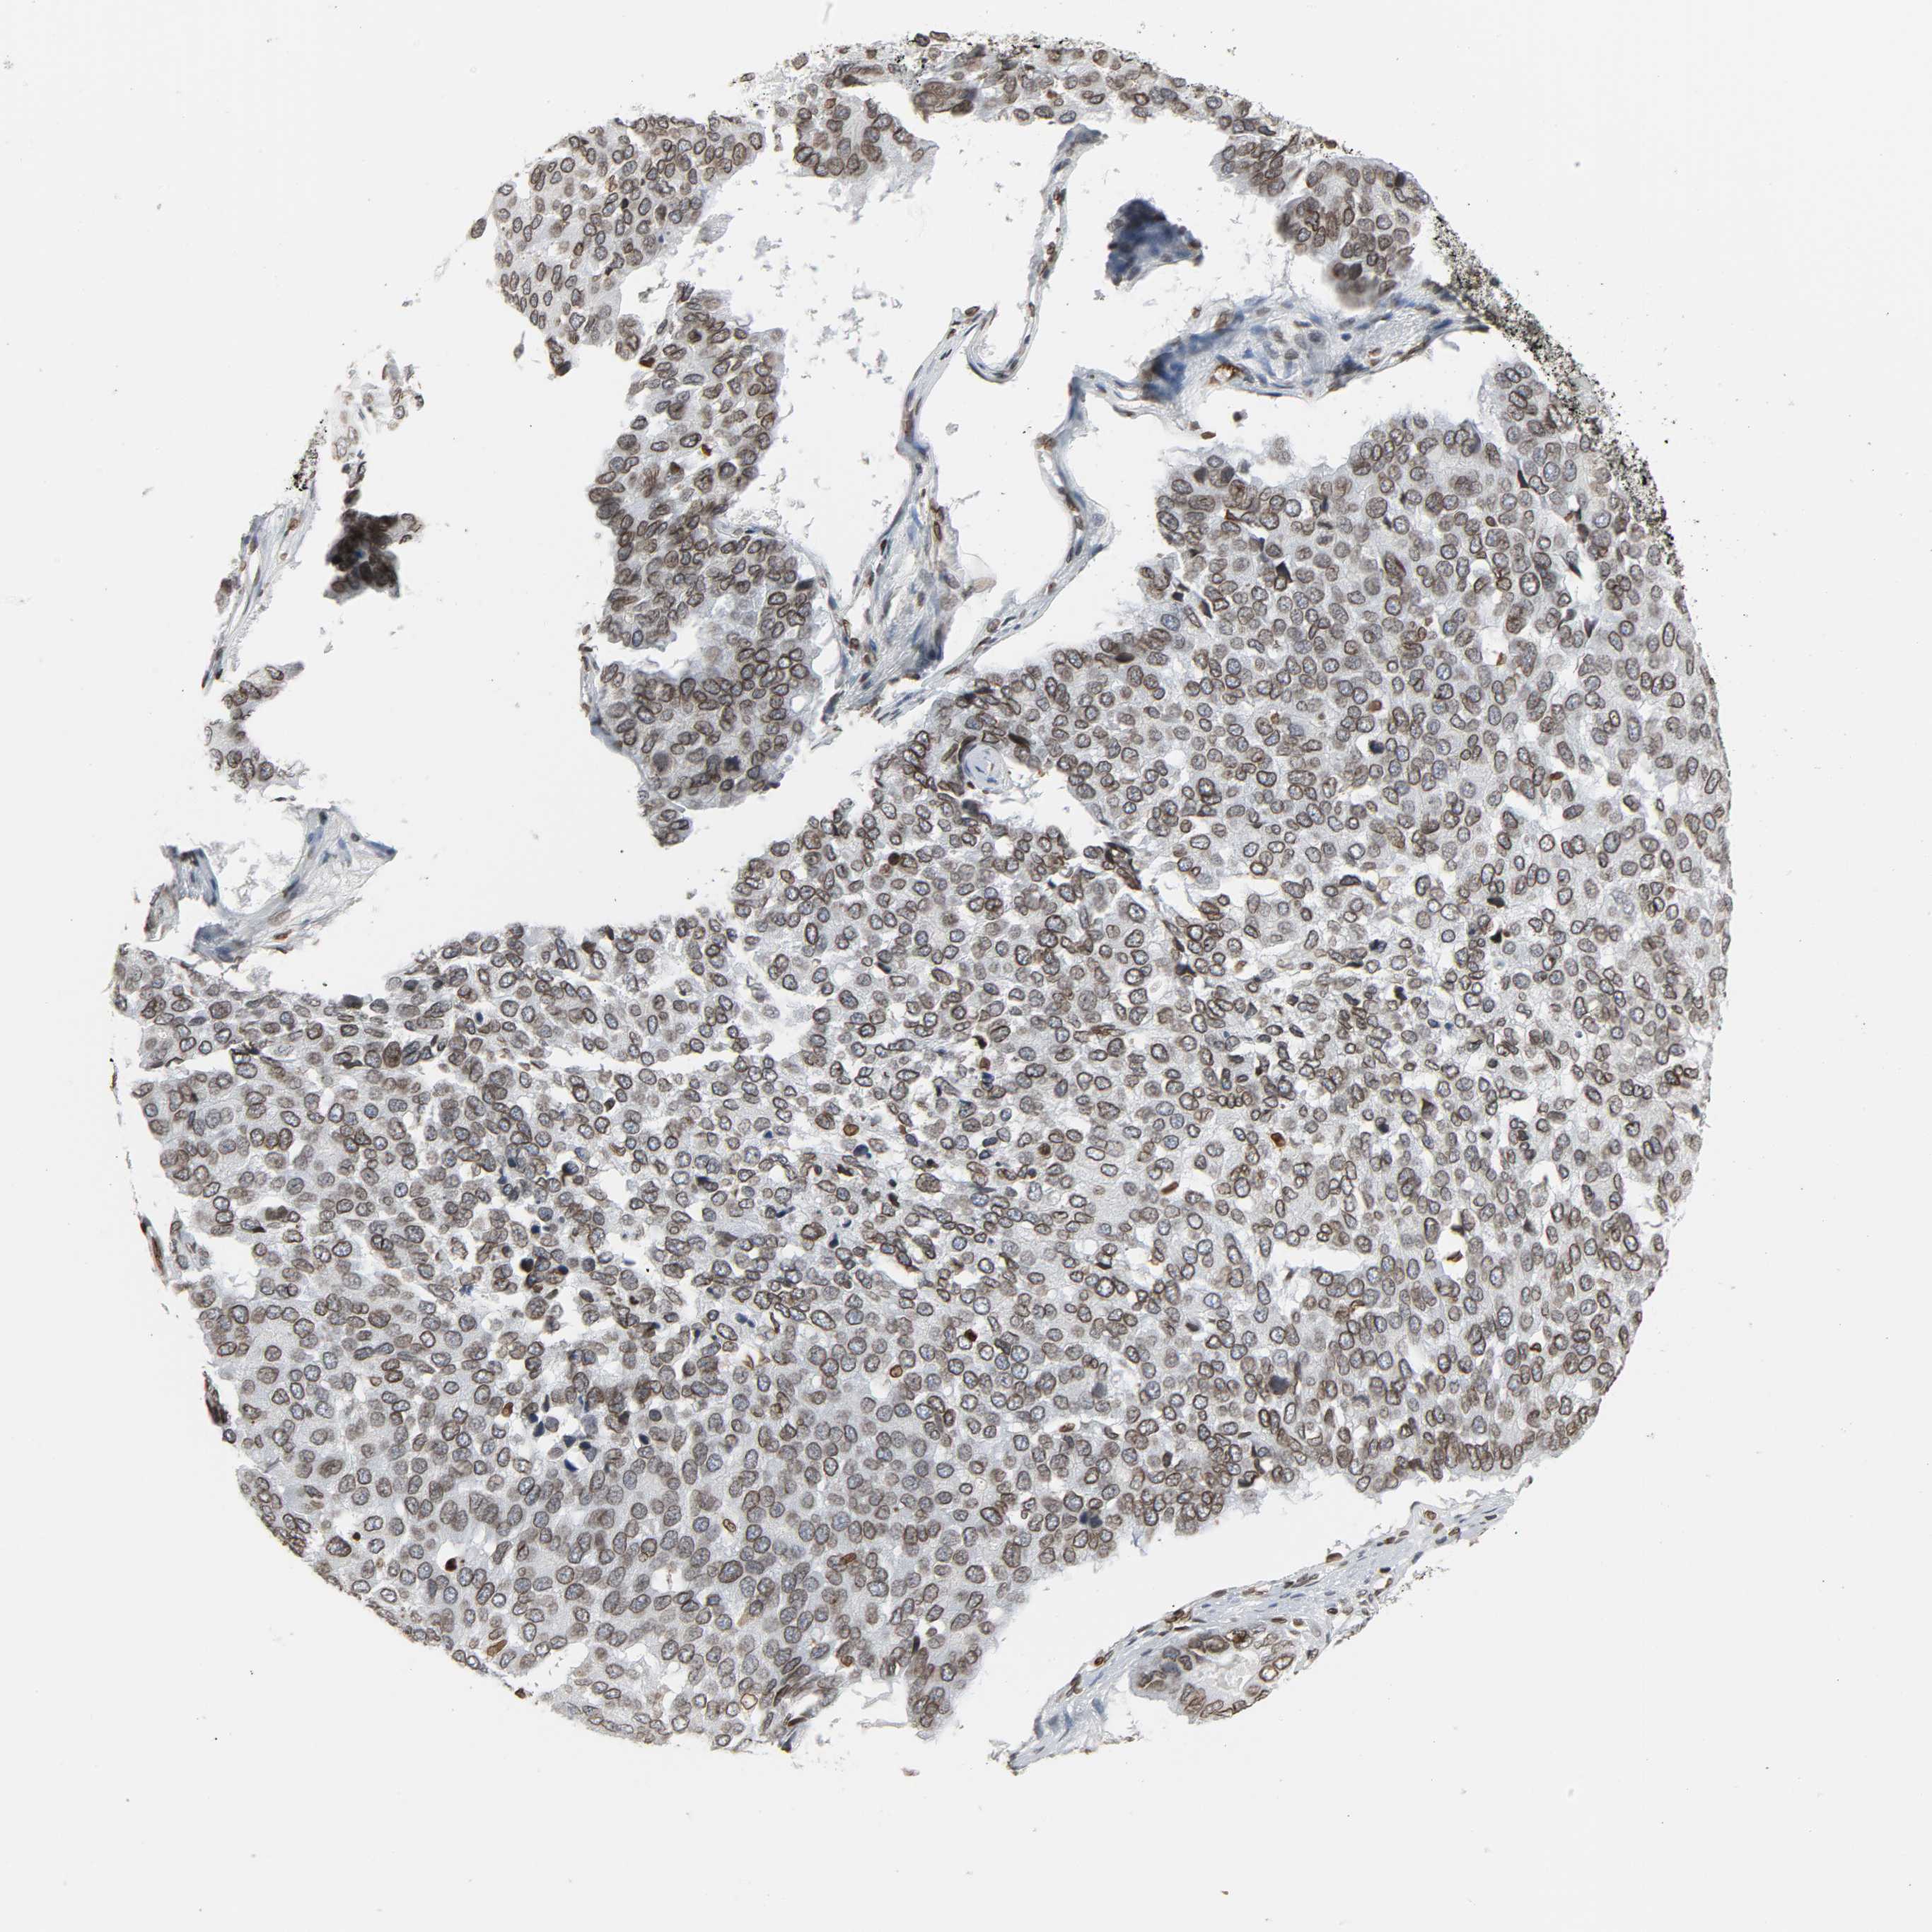

PANCREATIC CANCER - Protein expressioni

A mouse-over function shows sample information and annotation data. Click on an image to view it in a full screen mode. Samples can be filtered based on level of antibody staining by selecting one or several of the following categories: high, medium, low and not detected. The assay and annotation is described here.

Note that samples used for immunohistochemistry by the Human Protein Atlas do not correspond to samples in the TCGA dataset.

Antibody stainingi

Antibody staining in the annotated cell types in the current human tissue is reported as not detected, low, medium, or high, based on conventional immunohistochemistry profiling in selected tissues. This score is based on the combination of the staining intensity and fraction of stained cells.

Each image is clickable and will lead to virtual microscopy that enables deeper exploration of all samples and also displays staining intensity scores, fraction scores and subcellular localization as well as patient and tissue information for each sample.

Antibody HPA004246

Antibody CAB018641

Staining

High

Medium

Low

Not detected

Intensity

Strong

Moderate

Weak

Negative

Quantity

>75%

75%-25%

<25%

None

Location

Nuclear

Cytoplasmic/membranous

Cytoplasmic/membranous,nuclear

Adenocarcinoma, NOS

Adenocarcinoma, metastatic, NOS